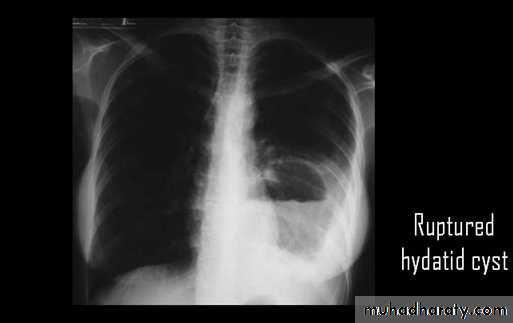

Ruptured hydatid cyst (water lily sign)

Ruptured H.C. With water lily sign .

chest practice